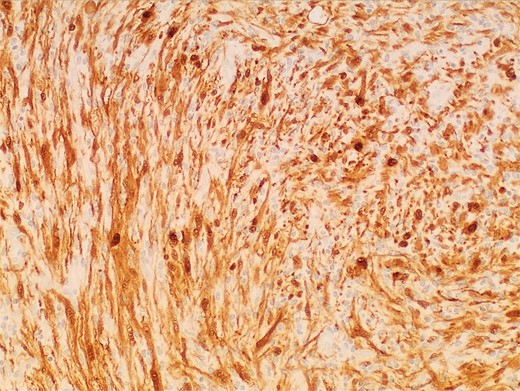

Gross examination and cut sections revealed fragments of tan–white to tan–yellow tissue with some areas of hemorrhage measuring from 1.1 to 3.6 cm in the greatest dimension. Histopathological examination of the excised mass confirmed the diagnosis of a retroperitoneal schwannoma, characterized by S100 positivity (Fig. 3) and degenerative changes, including hemorrhage, hemosiderin, and cystic degeneration (Fig. 4), nuclear atypia (Fig. 5), and perivascular hyalinization (Fig. 6).

Photomicrograph of diagnostic histopathology showing strong and diffuse S100 immunohistochemical stain uptake by lesional cells.